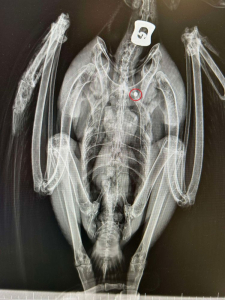

Lors de sa prise en charge dans notre clinique vétérinaire partenaire, une radiographie a révélé la présence d’un plomb logé dans sa cage thoracique, confirmant un tir de braconnage...

Radio Aigle de Bonelli © LPO PACA